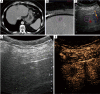

Background: To assess the technical success of contrast enhanced ultrasound (CEUS) guided biopsies of liver lesions poorly visualized on B-mode ultrasound.

Methods: Patients were selected during the procedure based on the real-time clinical scenario of unsatisfactory B-mode ultrasound lesion visualization and all patients would have otherwise undergone CT guided liver lesion biopsy. A total of 26 patients underwent CEUS guided biopsy and were included in this retrospective analysis. The review of the patients' files included demographic information, lesion characteristics on imaging, procedural details and pathology outcome. Technical success was defined as concordance between the radiological findings, pathology report and clinical follow-up-demonstrating lack of need for re-biopsy or re-biopsy with identical pathological results. Patients with less than 2 months follow-up were excluded from the study.

Results: CEUS guided liver biopsy was successful in 23 out of 26 patients (88.5%). The average procedure time was 30.7±12.3 minutes and the average lesion size was 2.2±1.7 cm. The majority of lesions (80.8%) were hypoenhancing on the delayed phase of CEUS. The mean number of samples taken from each lesion per procedure was 3.2 (±1.7).

Conclusions: CEUS guidance biopsies of focal liver lesions (FLL) that were difficult to visualize on B-mode ultrasound demonstrated high success rate and may be an evolving image guidance modality in selected patients to avoid CT guided procedures.